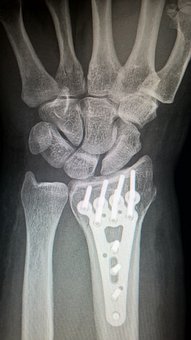

그곳에서는 검사 결과상 나의 왼쪽 손목이 아주 오래전 외상을 입었고 그로 인해 뼈가 튀어나오면서 손목의 근육에 염좌를 일으켰다는 것이었다. 진료를 보고 곰곰히 생각해보니 어린 시절 다쳤던 때를 기억하게 되었다.

그 외상으로 인해 생긴 염좌였다는 사실을 알게 되었고 총 3가지의 시술을 받았다.

결론적으로는 수술을 하라는 권유받았다. 튀어나온 뼈를 잘라 맞추는 수술이었다.